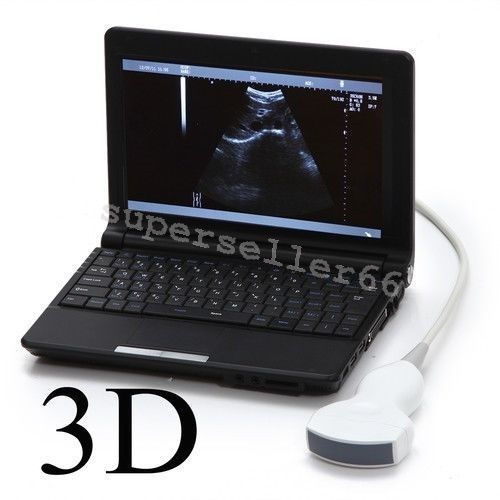

Ultrasound Scanner Laptop Machine Ultrasonic Machine Convex Rectal Transducer

Ultrasound Scanner machine Rectal Probe 3D Laptop Machine Digital Veterinary AA 190891879431

Ultrasound Scanner Veterinary Pregnancy US-96 with 3.5 MHz Convex Probe.

Ultrasound Scanner Veterinary Pregnancy US-96 with 7.5 MHz Rectal Probe.